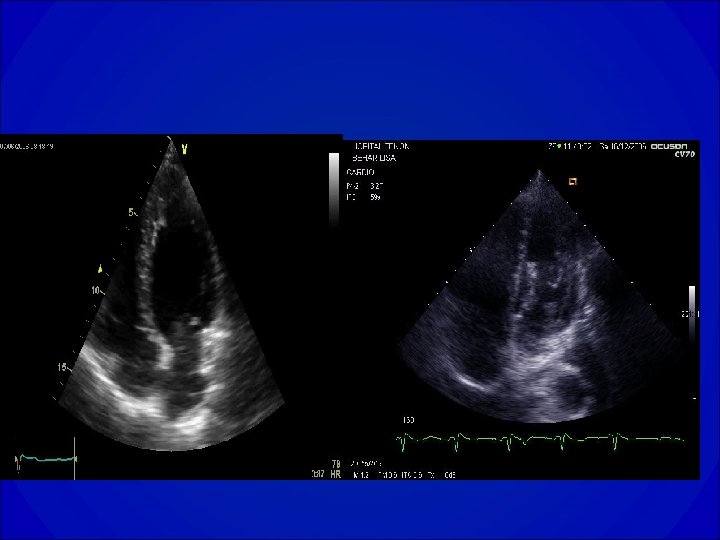

ECHOCARDIOGRAPHIE • Orientation étiologique et bilan de sévérité de la maladie • Evaluation de la fonction VG globale (dilatation ? Hypertrophie ? Fraction de raccourcissement, fraction d’éjection), cinétique segmentaire • Recherche d’une valvulopathie et évaluation de sa sévérité • Evaluation de la PAPS

Estimation des diamètres VG

VG normal Dysfonction VG